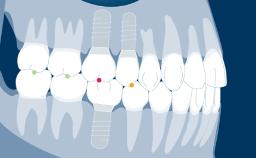

Um pilar de implante é a parte ou componente que serve como suporte e/ou retenção para uma prótese dentária. A seleção do pilar do implante para cada paciente é, portanto, uma parte importante da fase de tratamento com implante-prótese. Neste módulo, discutiremos a função dos pilares de implantes, diferentes tipos de pilares para implantes, diferentes materiais de pilares e como selecionar um pilar com base em um processo determinado pela prótese.

- identificar diferentes tipos de pilares de implantes

- selecionar pilares baseados em indicações protéticas e planejamento